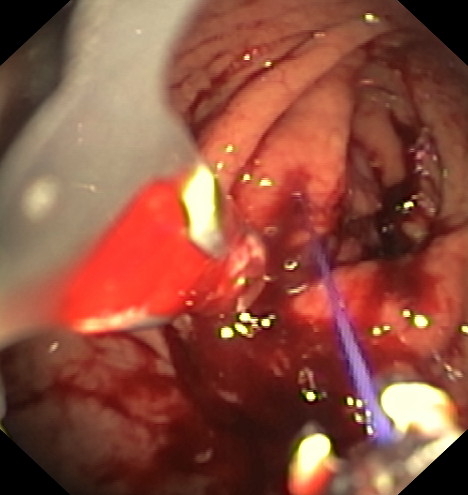

La gastroplastia endoscópica mediante la técnica endomanga se realiza por el gastroscopia, bajo anestesia general y dura aproximadamente entre 25 y 35 minutos. Mediante la endoscopia se realizan unos 18 pliegues definitivos a lo largo de todo el cuerpo gástrico, reduciendo de manera importante su capacidad de apertura, acortándolo y estrechándolo. Gracias a esta reducción los pacientes disminuyen la sensación de hambre.

Mediante un sistema de sutura acoplado a un endoscopio, se sutura el estómago “desde dentro” dándole un aspecto similar al conseguido por la cirugía de gastrectomía vertical laparoscópica (manga gástrica quirúrgica), pero con menor riesgo quirúrgico y muy buenos resultados a medio y largo plazo. De esta manera se limita la cantidad de comida que puede entrar en el estómago e igualmente hace que la digestión sea más lenta, favoreciendo enormemente la saciedad y la pérdida de peso. Es una técnica definitiva, pero por vía oral, ni realizar heridas abdominales ni cicatrices.